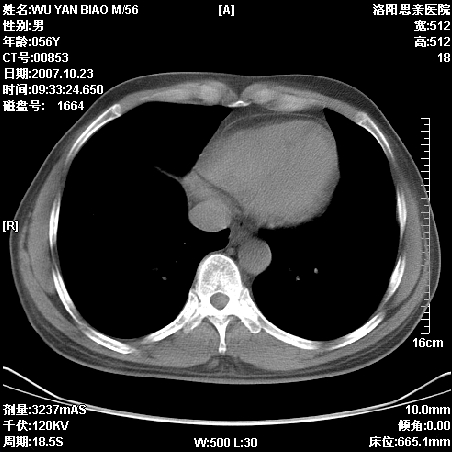

标题: CT10160:M56Y,体检发现,病人无不适,病人随访中

后上纵隔占位,与肺交界清,宽基底附着脊柱,密度均匀,局部骨质无明确改变.

考虑;神经源性肿瘤,---起源交感n链?,不除外肠源性囊肿.

1、病灶在后纵隔脊柱旁沟内,此处是神经原性肿瘤的好发部位

2、病灶边缘光滑整齐,更说明病灶来于纵隔,由于有胸膜的包裹所以才导致这么光滑的边缘

3、病灶内的密度均匀